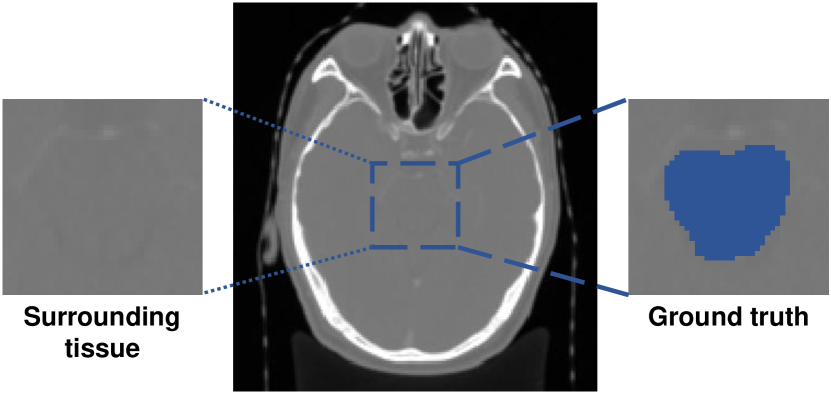

Figure 5: Visualization example of low contrast between brain stem and surrounding tissue in StructSeg19.

Without being indicated the range of slices where the organ lies, our proposed PRNet outperforms others largely, especially in StructSeg19. There are mainly 2 reasons: (1) SE-Net passes the support set through the conditioner arm, whose information is conveyed to the segmenter arm via interaction blocks. It assumes that the target organ in the support slice is roughly aligned with the one in the query. However, due to the limited volume size of organs in HaN, even slight intersecting pixels of target organs between support and query slices caused by small variance among patients could make the above assumption unsatisfied. Fig. 4 presents an visualization example of parotid glands. It could be observed that the propagation of the support mask on query slice has a small overlap with the ground truth; (2) SSL-ALPNet utilizes a self-supervised superpixel segmentation task then uses the learned representations to segment new classes without fine-tuning. However, as shown in Fig. 5, the contrast of organs, e.g., brain stem in StructSeg19 with surrounding tissue, is extremely low even after normalization, which is vital to SSL-ALPNet because it could hardly select superpixels distinguishing the boundary of target organs during training time. In contrast, our method first locates fore-/background scribbles in query volumes, thus is not sensitive to the extreme sample imbalance and low contrast.